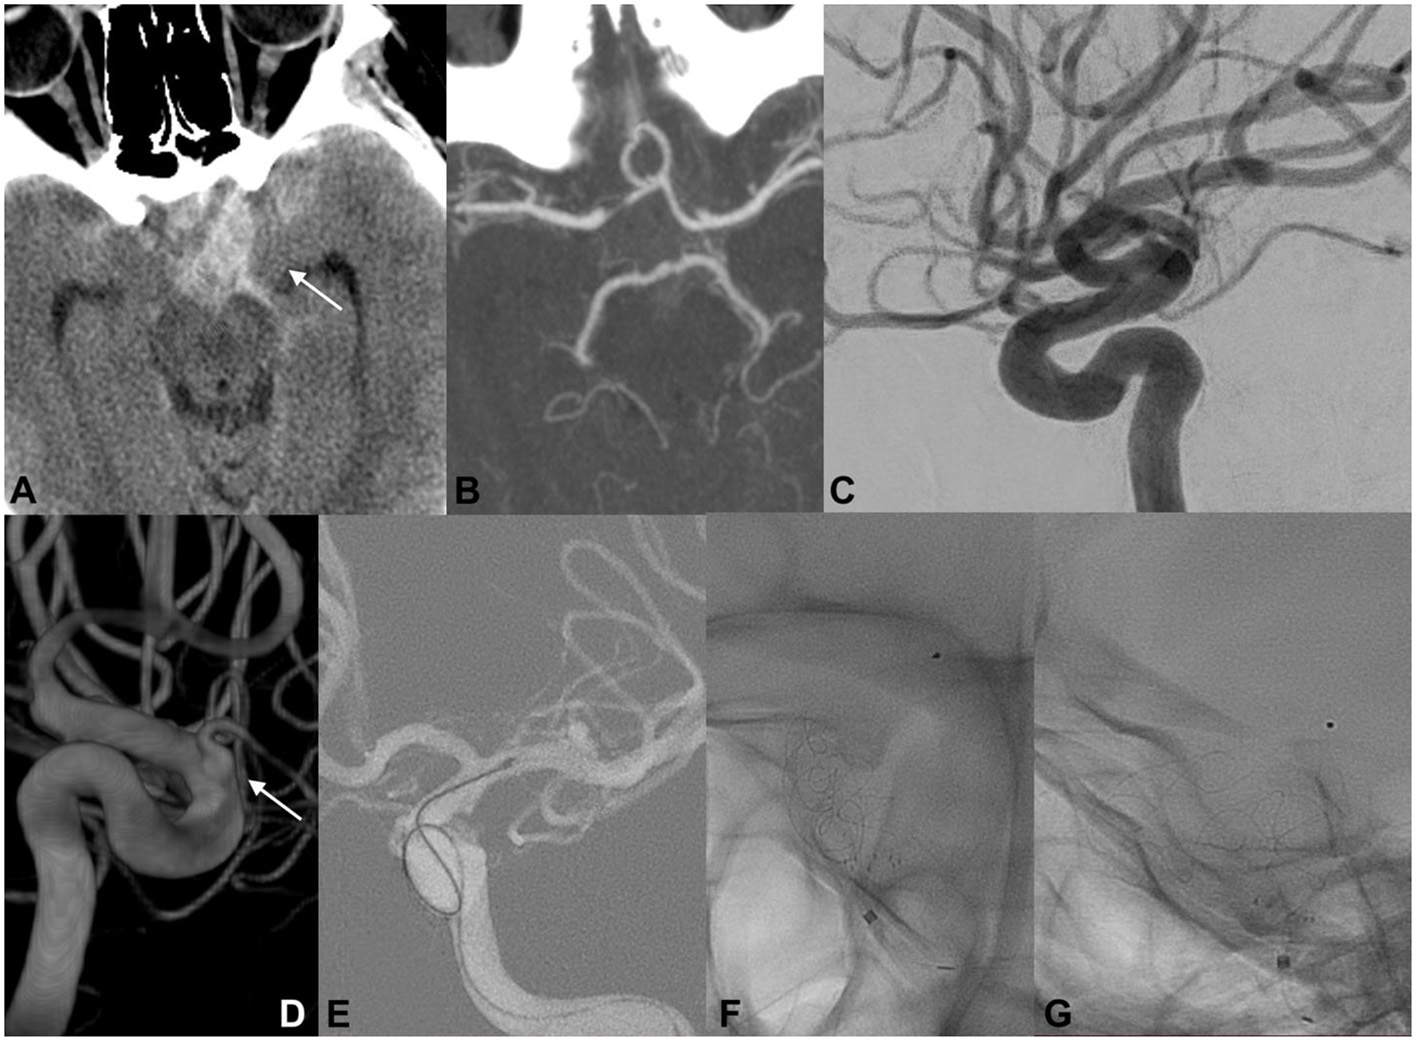

A 46-year-old woman was admitted to another hospital for a sudden thunderclap headache (Figure 2). CT revealed diffuse SAH with increased blood collection in the left suprasellar cistern and left-sided Sylvian fissure. Subsequent CTA did not confirm the presence of any cerebrovascular findings that could be responsible for the acute SAH. DSA did not detect any intracranial aneurysms but revealed an ID at the origin of the left PcomA. The delayed 3DRA/DSA 7 days after onset identified a possible rupture bleb on the lateral side of the left PcomA ID. The patient had a history of an identical episode occurring 5 years earlier, but the radiological examinations did not confirm any intracranial hemorrhage. The patient's medical records included trombangiitis obliterans (Buerger disease), idiopathic thrombocytopenic purpura, and uncontrolled hypertonia. On the basis of the above findings, we concluded that the tiny bleb on the PcomA ID was responsible for the intracranial hemorrhage. Endovascular coil embolization of the ruptured infundibular bleb was performed but was unsuccessful. Coiling of the ruptured dilatation was not possible because the coils protruded toward the parent artery's lumen. Bailout flow diversion was considered appropriate for this case. The patient received a bolus dosage of glycoprotein IIb/IIIa–tirofiban and received a p64 (phenox, Bochum, Germany) FD. Contrast stagnation inside the ruptured bleb was observed on the final angiograph. The patient was discharged after 14 days with no new neurological deficits detected.

Figure 2. EVT of a ruptured PcomA ID. An initial CT scan demonstrated the presence of SAH predominantly distributed across the left basal cisterns (A; white arrow). Cranial CTA did not document any cerebrovascular findings that could have caused the SAH (B). At 6 h after onset, catheter angiography confirmed the absence of a ruptured aneurysm but revealed a typical ID at the origin of the left PcomA (C). Delayed 3DRA/DSA (D,E; white arrows) 7 days after onset identified a possible rupture bleb on the lateral side of the left PcomA ID. Endovascular coil embolization of the ruptured bleb was unsuccessful, and a p64 FD was carefully deployed across the C7 segment of the left ICA (F,G). Contrast stagnation inside the ruptured ID bleb was seen on the delayed angiographic phase (not provided).